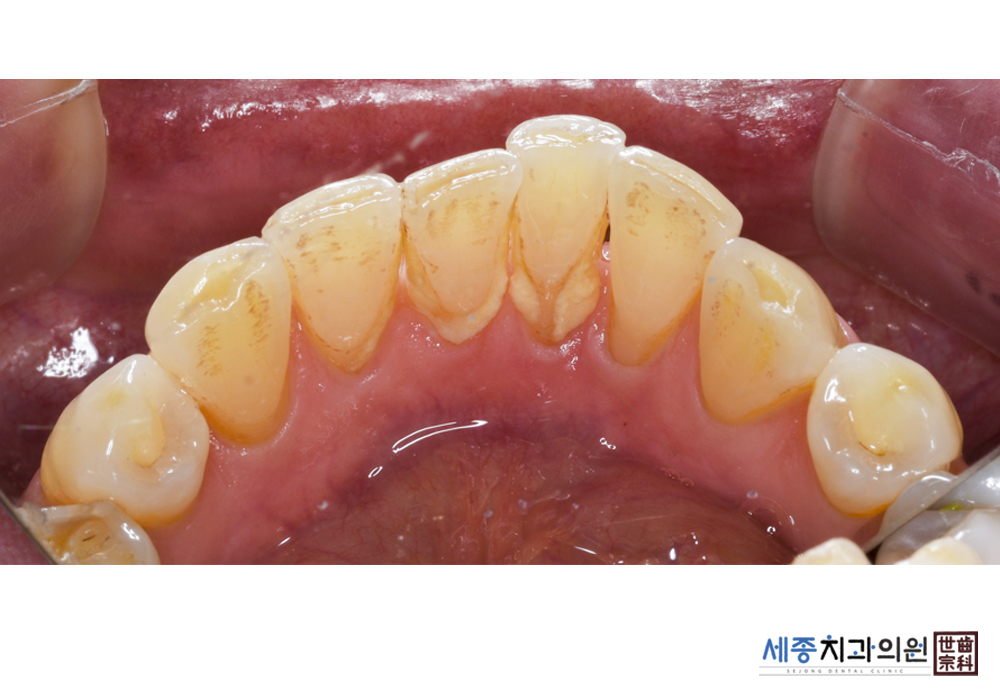

[스케일링] 치주질환 예방 스케일링 치료

치료전 : 2020-01-02

치료후 : 2020-01-02

가글마취&저주파 스켈러를 사용한 스케일링